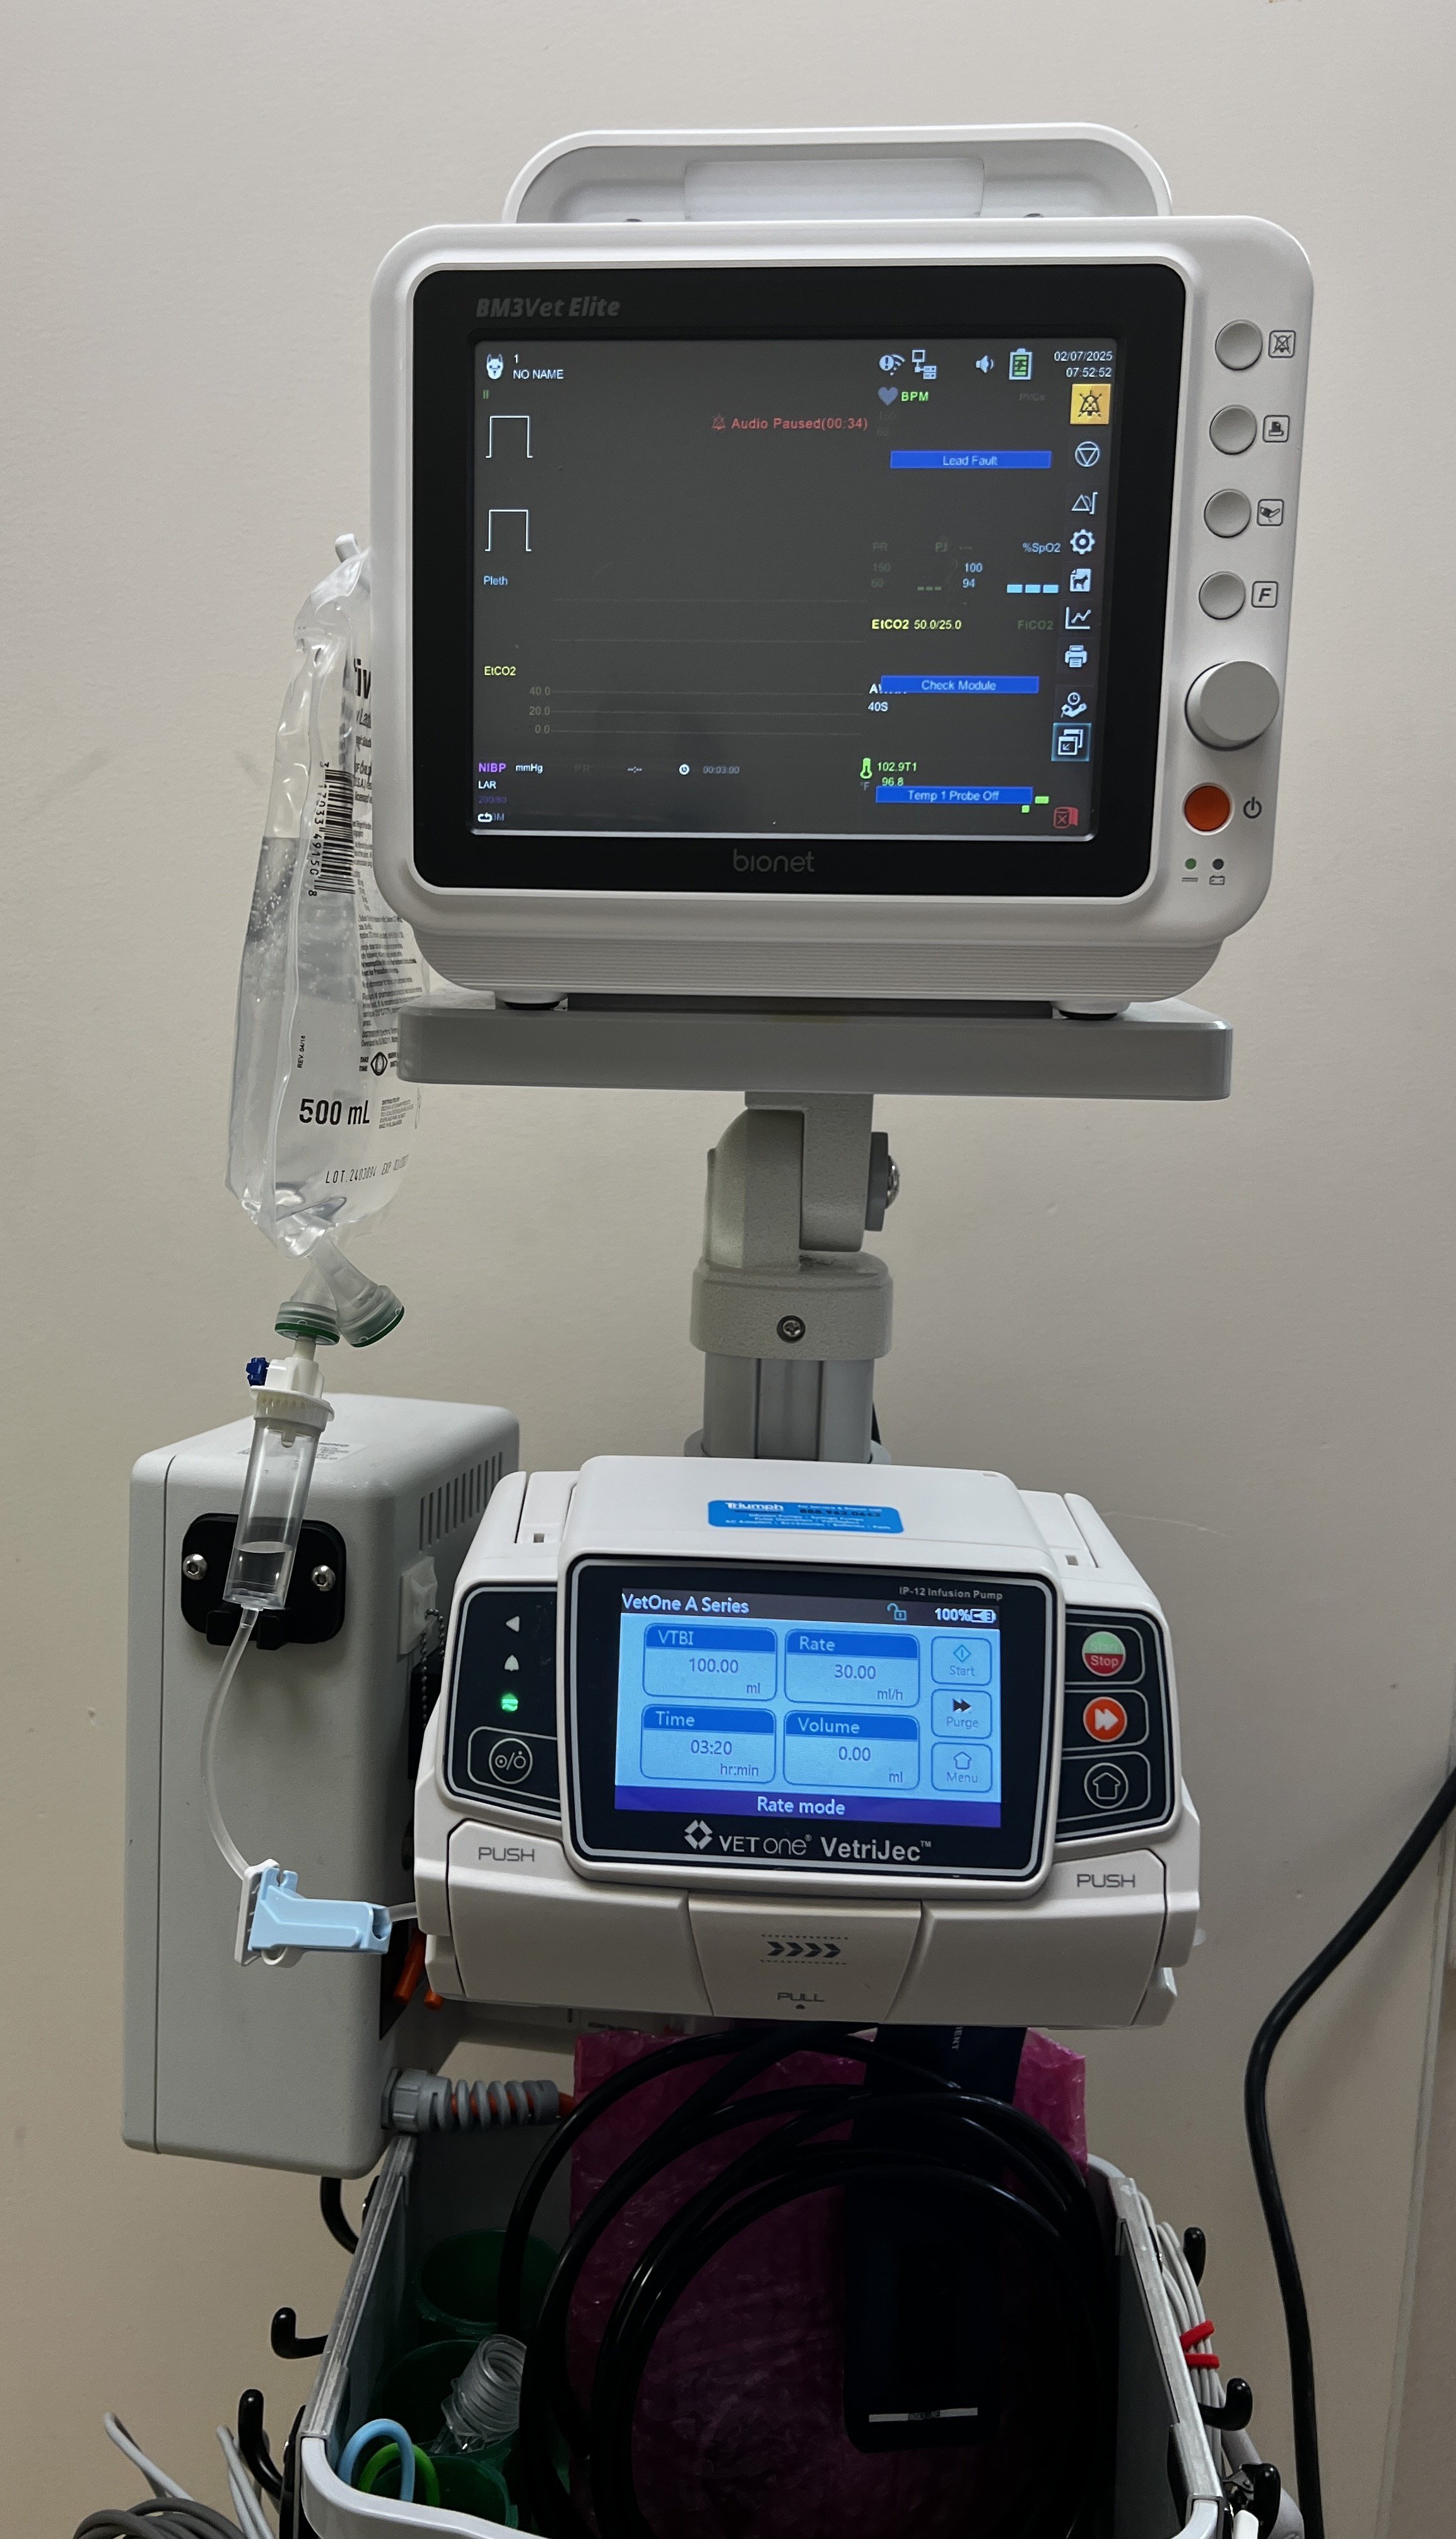

Canine patient receiving IV fluid therapy.

At some point in their life, your dog or cat will need more than preventive health care. Kingdom’s medical team is here to help, with advanced diagnostic and medical care. We will give you confident assurance that with our highly trained medical staff, your pet is in the very best hands possible. We perform diagnostics including bloodwork, radiographs, and ultrasound during your appointment whenever possible, so you can get the answers you need for your sick pet and start the appropriate treatment plan right away.